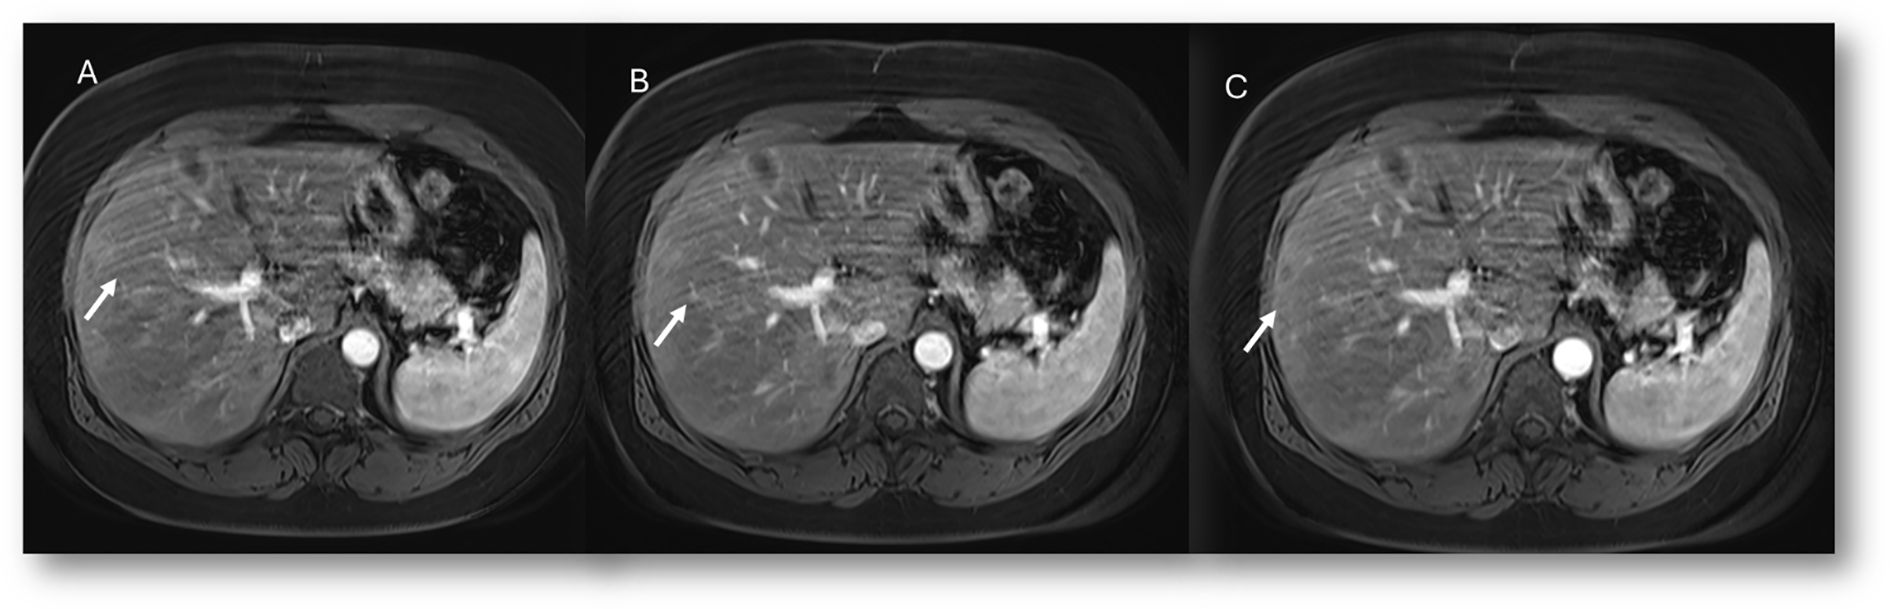

Figure 2. MRI assessment of non-mucinous colorectal liver metastases (arrows). In (A) (T2-W sequence, axial plane), the lesion (arrow) shows hyperintense signal with restricted diffusion on b = 880 s/mm² (B) and targetoid appearance on ADC map (C). After non-specific contrast agent, rim enhancement is seen in the arterial phase (D, T1-W, axial), with peripheral enhancement in the portal (E) and late phases (F) showing targetoid appearance from central necrosis.

Figure 3. MRI assessment of mucinous colorectal liver metastases (arrows). In (A) (T1-W sequence, axial plane), the lesion (arrow) shows hypointense signal, with very high signal on T2-W FS sequence (B) and restricted diffusion on b = 880 s/mm² (C). After non-specific contrast agent, rim enhancement is seen in the arterial phase (D, T1-W, axial), with progressive enhancement in the portal (E) and late phases (F).